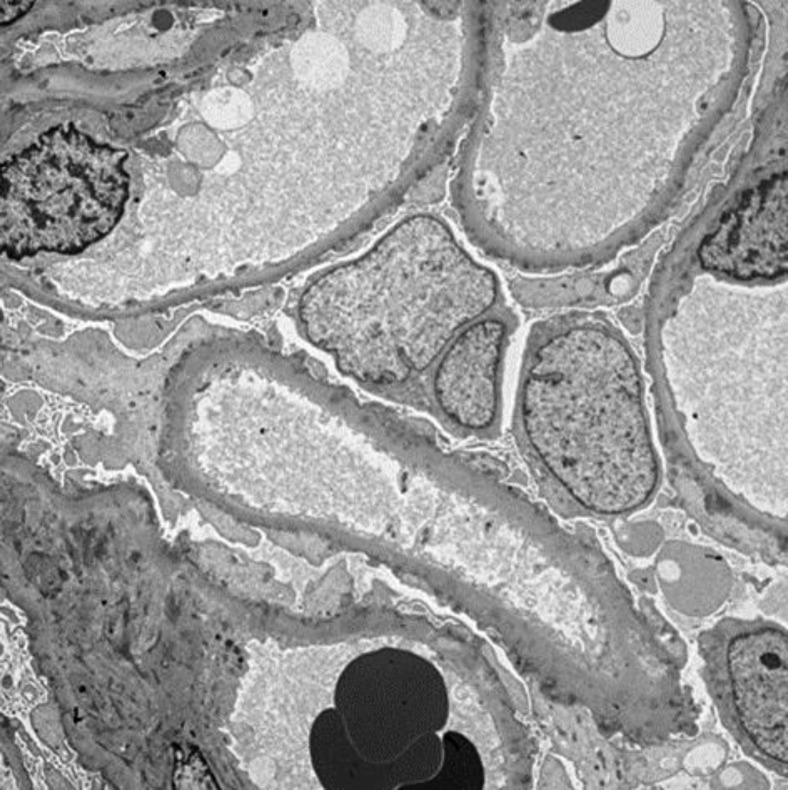

Membranous nephropathy (MN) is one of the most common causes of nephrotic syndrome (NS) in adults. It may be primary, usually mediated by IgG4 anti-phospholipase A2 autoantibodies or secondary to various other conditions. Guillain- Barré syndrome (GBS) has been associated with MN, but a cause and effect relation has not been proven. We present a case of concurrent development of GBS and severe NS, with renal biopsy demonstrating MN. IgG4 stain was negative, indicating that most likely, the MN was secondary and probably caused by the underlying GBS.